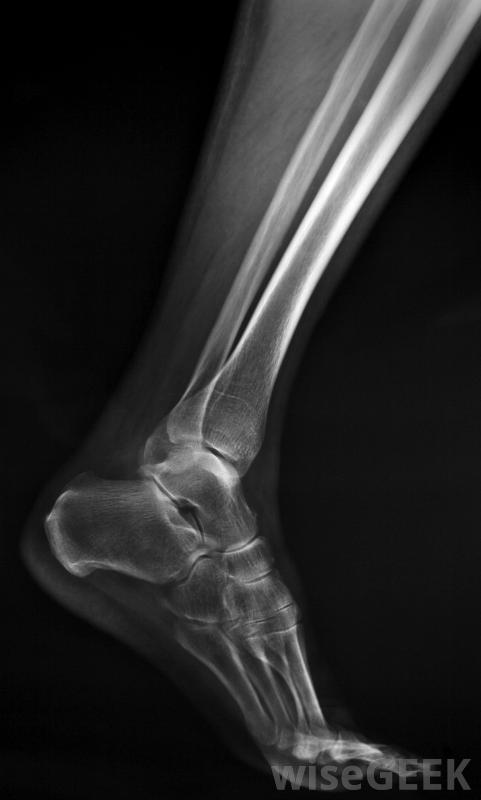

踝关节融合术是一种将小腿胫腓骨和踝关节距骨的关节融合在一起的手术,这种手术通常用于治疗严重的踝关节疼痛,通常是由关节炎引起的。它通常只适用于那些尝试过非手术治疗的患者,例如经过特殊改造的鞋子和止痛药,但没有成功。踝关节融合通常用于年轻、活动更活跃的患者,作为人工踝关节置换术的替代方案,因为融合的关节更多踝关节融合术是距骨与胫腓骨之间的关节融合的一种手术踝关节融合术包括将踝关节距骨与小腿胫骨和腓骨的末端固定在一起。在将骨头表面整平以去除受损的骨和软骨后,金属螺钉是用来将它们固定在一起的。作为愈合过程的一部分,新骨的形成将切割面结合并融合关节。踝关节随后变得僵硬,但脚和膝盖的柔韧性有助于弥补这一点,尽管跑步可能无法进行,但患者通常能够正常行走关节融合术后,通常需要三个月左右才能完成融合,因此关节需要休息,在此期间可能需要戴石膏

由于踝关节(由胫骨和距骨组成),脚能够旋转,与腓骨远端一起。